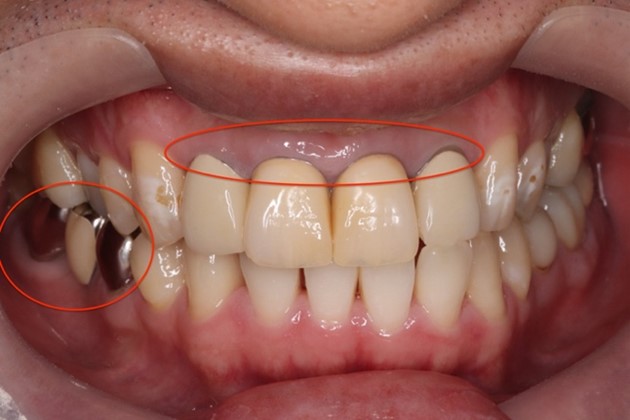

他院にて、数年前に前歯の治療をされましたが、次第に色が黄ばみ、最近では歯と歯茎の境目(右写真赤丸)が気になり始めたとのことです。右下(写真左下赤丸部位)の銀歯も白くしたいというご要望がありました。